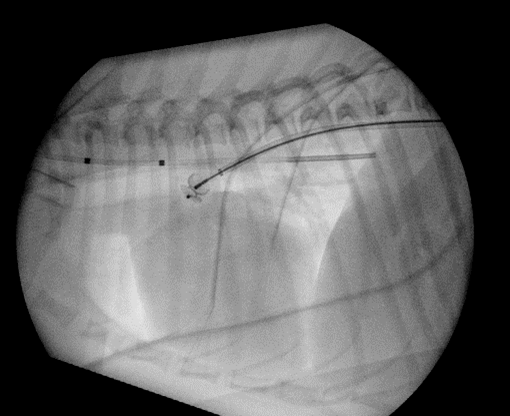

There is no proven benefit of any medical therapy for asymptomatic dogs with left-to-right PDA. If CHF is present, routine therapy should be started. Surgical closure of the PDA is considered the treatment of choice (Figure 3). This can be achieved via thoracotomy or minimally invasive techniques, such as transarterial occlusion with devices like the Amplatz Canine Duct Occluder (ACDO) (Figure 4) or Amplatzer Vascular Plug (AVP).